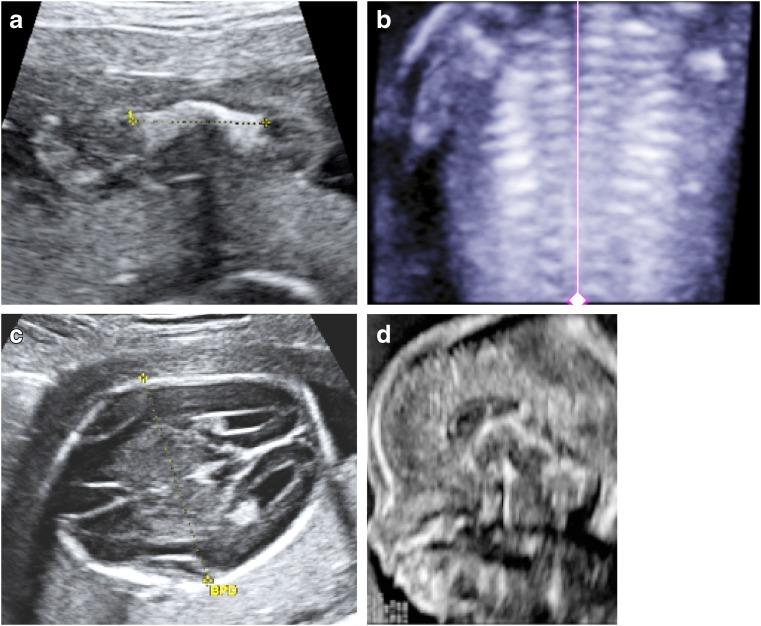

Perinatal hypophosphatasia (HPP) is a rare, potentially life-threatening, inherited, systemic metabolic bone disease that can be difficult to recognize in utero and postnatally. Diagnosis is challenging because of the large number of skeletal dysplasias with overlapping clinical features. This review focuses on the role of fetal and neonatal imaging modalities in the differential diagnosis of perinatal HPP from other skeletal dysplasias (e.g., osteogenesis imperfecta, campomelic dysplasia, achondrogenesis subtypes, hypochondrogenesis, cleidocranial dysplasia). Perinatal HPP is associated with a broad spectrum of imaging findings that are characteristic of but do not occur in all cases of HPP and are not unique to HPP, such as shortening, bowing and angulation of the long bones, and slender, poorly ossified ribs and metaphyseal lucencies. Conversely, absent ossification of whole bones is characteristic of severe lethal HPP and is associated with very few other conditions. Certain features may help distinguish HPP from other skeletal dysplasias, such as sites of angulation of long bones, patterns of hypomineralization, and metaphyseal characteristics. In utero recognition of HPP allows for the assembly and preparation of a multidisciplinary care team before delivery and provides additional time to devise treatment strategies.

围生期低磷酸酯酶症(HPP)是一种罕见的、可能危及生命的遗传性全身性代谢性骨病,在子宫内和出生后都可能难以识别。由于大量骨骼发育异常具有重叠的临床特征,诊断具有挑战性。本综述重点关注胎儿和新生儿成像模式在围生期HPP与其他骨骼发育异常(如成骨不全、弯肢侏儒症、软骨发育不全亚型、低软骨发育不全、锁骨颅骨发育不全)的鉴别诊断中的作用。围生期HPP与一系列广泛的影像学表现相关,这些表现是HPP的特征性表现,但并非在所有HPP病例中都出现,也不是HPP所特有的,如长骨缩短、弯曲和成角,以及肋骨纤细、骨化不良和干骺端透亮区。相反,全骨无骨化是严重致死性HPP的特征,且与极少数其他病症相关。某些特征可能有助于将HPP与其他骨骼发育异常区分开来,如长骨成角部位、矿化不足模式和干骺端特征。在子宫内识别HPP可在分娩前组建和准备多学科护理团队,并为制定治疗策略提供更多时间。